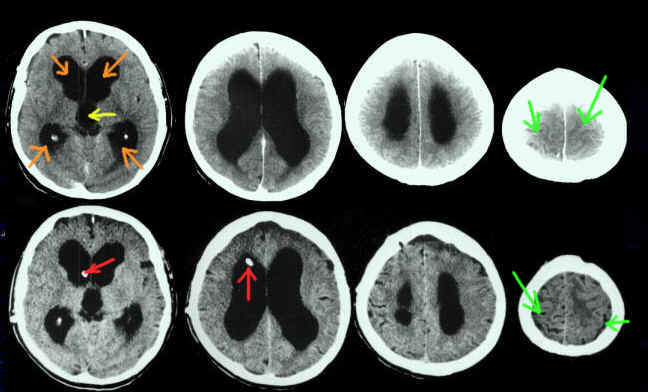

Die Abbildung zeigt eine Computertomographie (CCT) bei einem Patienten mit Normaldruckhydrocephalus: Die obere Bildreihe zeigt den Zustand vor Shuntanlage, die untere nach Shuntanlage. Die Schwarzen Flächen im Innern sind die Ventrikel (orangene Pfeile: Seitenventrikel im Großhirn; gelber Pfeil: III. Ventrikel im Zwischenhirn.

Auf den ersten Blick meint man, dass die Ventrikel vor und nach Shuntanlage (der Ventrikelkatheter des Shunts ist mit roten Pfeilen markiert) gleichgroß sind. Dies täuscht aber. Vermisst man die Ventrikel exakt, erkennt man, das sie etwas an Weite abgenommen haben. Darüberhinaus sieht man, dass die Hirnfurchen (grüne Pfeile) vor der Operation kaum zu sehen sind. Nach der Operation aber sind sie als schwarze Furchen an der Hirnoberfläche gut zu sehen.

MERKE: Eine suffiziente Therapie eines Hydrocephalus, - gleich mit welcher Operationsmodalität -, muß, um erfolgreich zu sein, nicht zu einer Normalisierung der Weite der Ventrikel führen. Vielmehr tritt dies nur bei Hydrocephaluserkrankungen ein, die nicht lange bestanden. Bei allen Formen des chronischen Hydrocephalus dagegen, ist durch die Erkrankung Hirngewebe untergegangen, das um die Ventrikel lag. Es ist klar, dass dieses auch nach Anlage eine Shunts nicht zurückkehrt und daher die Ventrikel weiter bleiben als es ohne diese Erkrankung sein sollte. Die Therapie des Hydrocephalus kann nur das Hirngewebe bewahren, das noch vorhanden ist.